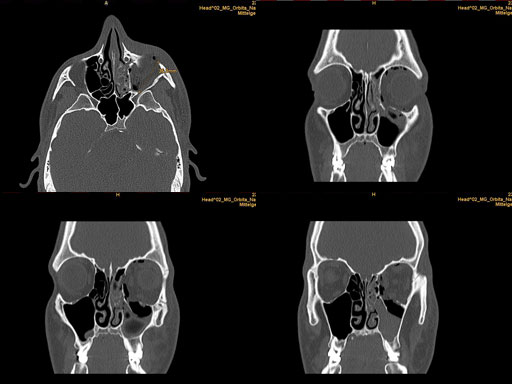

30 year old male patient with fracture of left orbital floor and medial wall.

Provided by Dr Dr Marc C Metzger, Freiburg, Germany.